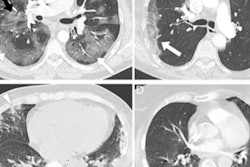

Unlike the FDG-PET/CT pattern seen with infections from previous strains of SARS-CoV-2, with principal involvement of the lungs, this new array of findings is primarily centered in the upper aerodigestive tract and cervical lymph nodes, the task force reported.

Specifically, there is prominent, symmetric FDG uptake throughout the nasopharynx, oropharynx, and tonsils (Waldeyer's ring) with or without associated FDG-avid cervical lymphadenopathy, particularly in the suprahyoid neck.

FDG uptake on PET/CT in nasal-associated lymphoid tissue in a cancer patient infected with the COVID-19 omicron variant. Image courtesy of Dr. Munir Ghesani.Dr. Munir Ghesani, chief of nuclear medicine and molecular imaging at Mount Sinai Health in New York City and chair of the SNMMI COVID-19 Task Force, said he began noticing what appeared to be a consistent pattern about a week ago and quickly confirmed similar findings on FDG-PET/CT in cancer patients with colleagues in Boston, Los Angeles, and Atlanta.